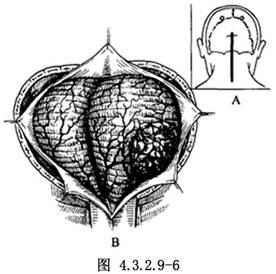

顱後窩中線切口。上起枕外粗隆上2cm,下至頸5棘突平面(圖4.3.2.9-6A)。腫瘤偏側方或前方時,宜採用枕下極外側入路。

3.探查腫瘤。切開硬腦膜,將之縫吊於周圍軟組織。腦膜瘤呈灰褐色或灰紫色,邊界清楚,基底附着於枕骨大孔側面的硬腦膜(圖4.3.2.9-6B)。